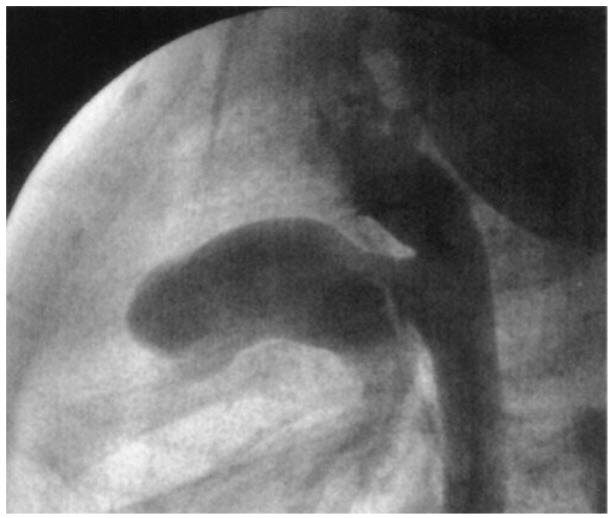

Match the following cardiac catheterization still-frame slide to it's respective diagnosis.

A. Coarctation of the aorta

B. Patent ductus arteriosus (PDA)

C. Hypertrophic cardiomyopathy

D. Pulmonic stenosis

E. Ventricular Septal Defect (VSD)